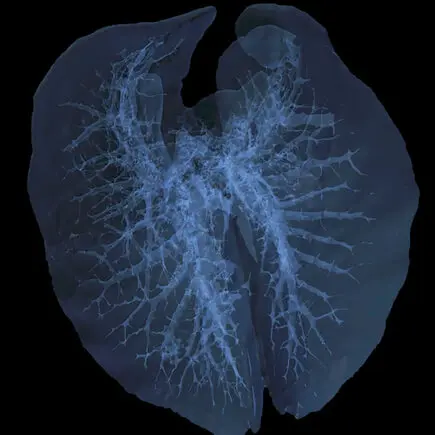

Metastaza nowotworu, znakowanie bioluminescencyjne: IVIS Spectrum CT